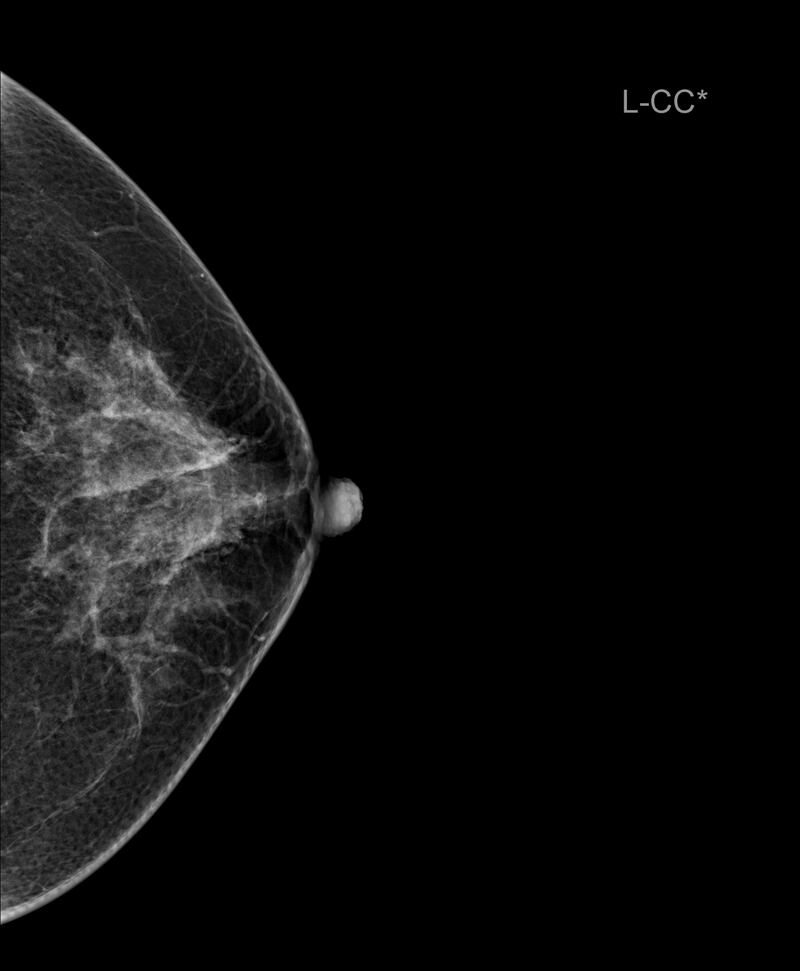

¿Qué es una mamografía?

“Una mamografía es una imagen de la mama tomada con rayos X que permite ver una imagen del interior de los senos. Existen mamografías de detección y mamografías de diagnóstico. Al realizarse una mamografía como especialista puedo detectar irregularidades en la mama o tumores que aún no se pueden sentir”, cuenta Clayreth Vinueza especialista en radiología.

Para la experta una mamografía debe realizarse a partir de los 40 años una vez todos los años. Además, que en mujeres con antecedentes de cáncer de mama o de varios se recomienda comenzar antes.